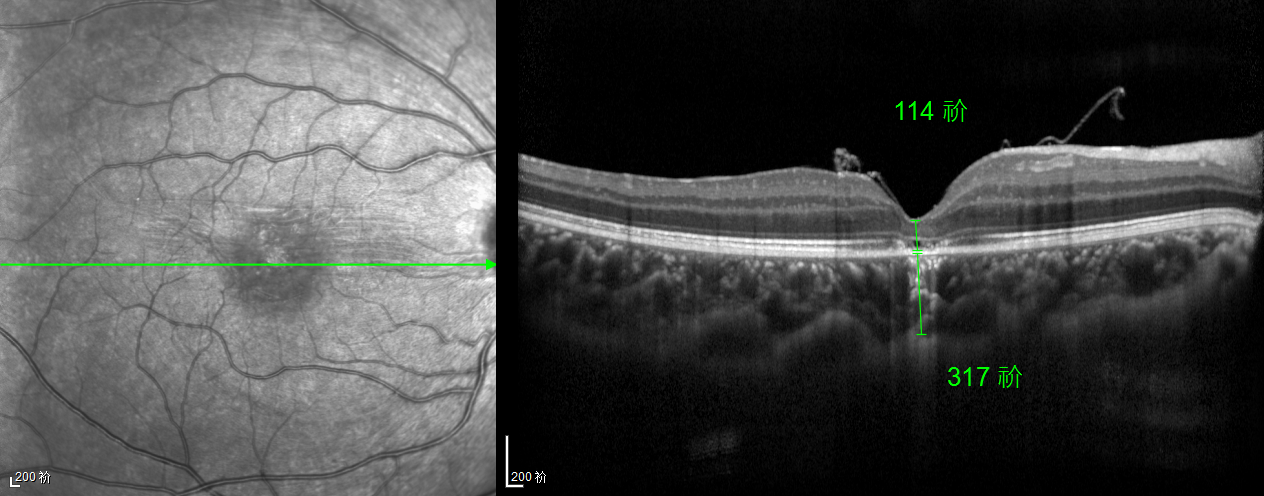

除此之外,利用自體組織覆蓋為黃斑裂孔提供了理想的愈合環(huán)境,裂孔閉合速度顯著快于傳統(tǒng)方法。誠誠接受手術(shù)24小時(shí)后,檢查可見內(nèi)界膜瓣位置良好;術(shù)后1個(gè)月,黃斑裂孔已經(jīng)閉合,視力恢復(fù)到0.5;術(shù)后兩個(gè)月,視力進(jìn)一步提升到0.7。

黃斑裂孔

術(shù)后1個(gè)月 △